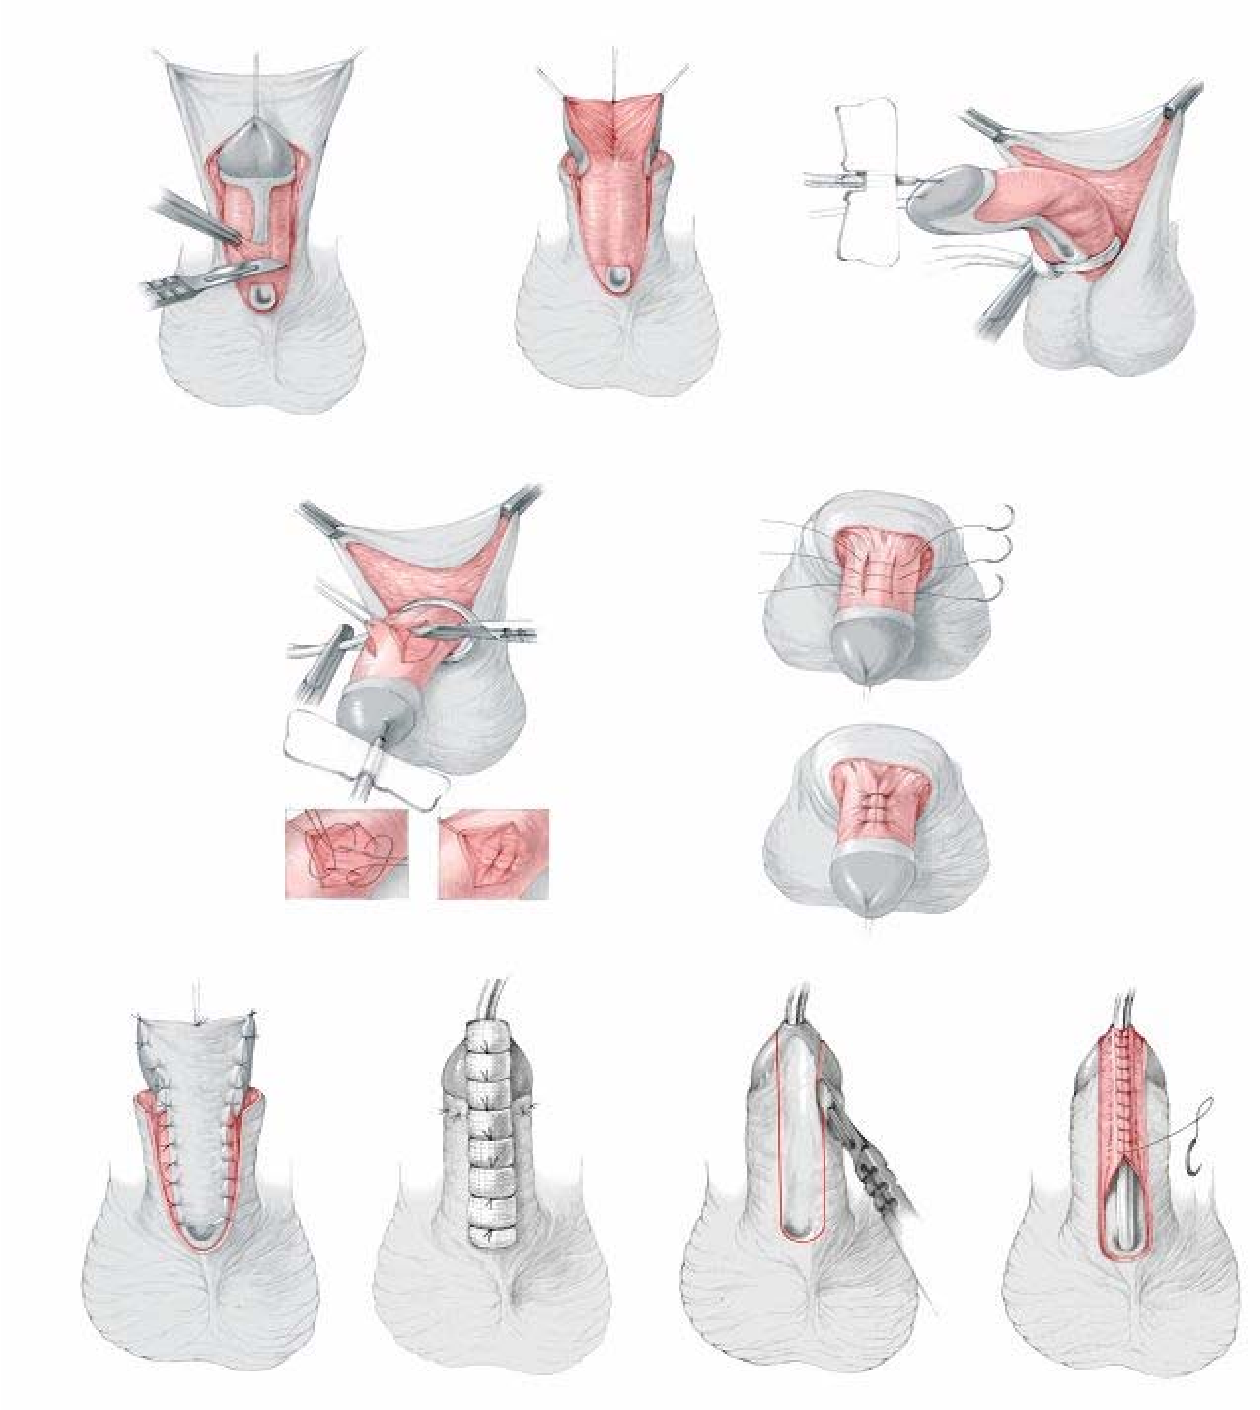

Процедура лабиопластики

Самым распространенным типом лабиопластики является процедура обрезки, при которой лишние ткани удаляются и непосредственно зашиваются.Следующей по популярности является процедура клина, которая сохраняет естественную границу после удаления кусочка ткани в форме пирога. Одновременно можно уменьшить лишние складки клиторального капюшона. Ушивание обычно выполняется рассасывающимися швами.

Лабиопластика, также известная как лабиопластика, заключается в хирургической модификации больших или малых половых губ, но чаще всего это уменьшение размера малых половых губ (рис.) и является одной из наиболее часто выполняемых процедур FCGS. Часто цель состоит в том, чтобы сохранить контур губ и сохранить цвет губных краев. Различные хирургические методы включают криволинейную резекцию, резекцию V-образным клином, резекцию нижнего клина и реконструкцию верхнего лоскута на ножке, Z-пластику и другие менее используемые методы.

При изогнутой линейной резекции [9, 10] можно выполнить одну из первых описанных техник, холодную резку, или использовать энергетическое устройство, такое как электрохирургическая игла, лазер или РЧ-генератор. можно использовать для резки.Губная ткань в объеме, необходимом для резекции, подвергается линейной резекции и скульптурированию по желанию, а затем края разреза ремонтируются рассасывающимся тонким швом. Целью этой техники является поддержание минимальной лабиальной длины в 1 см и возможность выступать за пределы интроитуса [11]. Сохранение естественного контура гофрированного свободного края с помощью этой техники невозможно. Однако это зависит от желания пациента, подвергающегося процедуре, и в одном исследовании с 550 женщинами 97% фактически потребовали удаления темных краев [12].К преимуществам относятся небольшие, относительно прямые половые губы, расположенные на одном уровне с большими половыми губами или расположенные ниже них с более розовым краем. Риски включают чрезмерную коррекцию или полную ампутацию, требующую хирургического вмешательства [13].

Резекция V-образным клином, первоначально описанная Alter [14], включает иссечение V-образного клина губной ткани, при этом верхний край V начинается немного ниже препуциальных складок, идущих вниз от капюшона клитора, а нижний край V начинается выше задней комиссуры.Преимущества включают предотвращение чрезмерной резекции и чрезмерного затягивания. Риски включают расслоение краев раны, образование свищей, избыток клиторального капюшона и послеоперационную боль. Резекция V-образным клином была изменена различными способами. Z-пластика [15] — это одна из модификаций, при которой центральный клин половых губ удаляется через разрез в форме буквы «Z». При резекции нижнего клина и реконструкции верхнего лоскута на ножке нижняя часть малых половых губ иссекается, а верхняя часть опускается в виде лоскута на ножке и фиксируется на обнаженном нижнем крае.

Вагинопластика предназначена для хирургического сужения влагалищного канала и включает удаление избыточной слизистой оболочки влагалища из сводов влагалища.Он может включать переднюю кольпорафию, заднюю кольпорафию, иссечение латеральной слизистой оболочки влагалища или различные комбинации этих хирургических методов (рис.). Некоторые хирурги также проводят пластику леватора по средней линии, чего, по нашему мнению, лучше всего избегать, так как это может вызвать выраженную диспареунию.

Лабиопластика, также известная как лабиопластика, заключается в хирургической модификации больших или малых половых губ, но чаще всего это уменьшение размера малых половых губ (рис.) и является одной из наиболее часто выполняемых процедур FCGS. Часто цель состоит в том, чтобы сохранить контур губ и сохранить цвет губных краев. Различные хирургические методы включают криволинейную резекцию, резекцию V-образным клином, резекцию нижнего клина и реконструкцию верхнего лоскута на ножке, Z-пластику и другие менее используемые методы.

При изогнутой линейной резекции [9, 10] можно выполнить одну из первых описанных техник, холодную резку, или использовать энергетическое устройство, такое как электрохирургическая игла, лазер или РЧ-генератор. можно использовать для резки.Губная ткань в объеме, необходимом для резекции, подвергается линейной резекции и скульптурированию по желанию, а затем края разреза ремонтируются рассасывающимся тонким швом. Целью этой техники является поддержание минимальной лабиальной длины в 1 см и возможность выступать за пределы интроитуса [11]. Сохранение естественного контура гофрированного свободного края с помощью этой техники невозможно. Однако это зависит от желания пациента, подвергающегося процедуре, и в одном исследовании с 550 женщинами 97% фактически потребовали удаления темных краев [12].К преимуществам относятся небольшие, относительно прямые половые губы, расположенные на одном уровне с большими половыми губами или расположенные ниже них с более розовым краем. Риски включают чрезмерную коррекцию или полную ампутацию, требующую хирургического вмешательства [13].

Резекция V-образным клином, первоначально описанная Alter [14], включает иссечение V-образного клина губной ткани, при этом верхний край V начинается немного ниже препуциальных складок, идущих вниз от капюшона клитора, а нижний край V начинается выше задней комиссуры.Преимущества включают предотвращение чрезмерной резекции и чрезмерного затягивания. Риски включают расслоение краев раны, образование свищей, избыток клиторального капюшона и послеоперационную боль. Резекция V-образным клином была изменена различными способами. Z-пластика [15] — это одна из модификаций, при которой центральный клин половых губ удаляется через разрез в форме буквы «Z». При резекции нижнего клина и реконструкции верхнего лоскута на ножке нижняя часть малых половых губ иссекается, а верхняя часть опускается в виде лоскута на ножке и фиксируется на обнаженном нижнем крае.

Вагинопластика предназначена для хирургического сужения влагалищного канала и включает удаление избыточной слизистой оболочки влагалища из сводов влагалища.Он может включать переднюю кольпорафию, заднюю кольпорафию, иссечение латеральной слизистой оболочки влагалища или различные комбинации этих хирургических методов (рис.). Некоторые хирурги также проводят пластику леватора по средней линии, чего, по нашему мнению, лучше всего избегать, так как это может вызвать выраженную диспареунию.